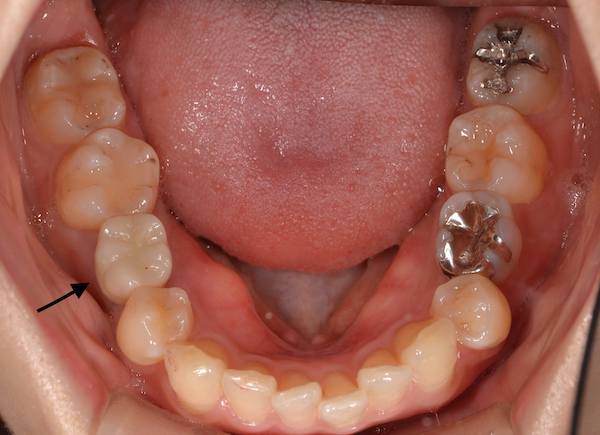

患者様は右下5番目の歯が先天的に欠損しており、大人になるまで乳歯が残っていましたが、歯の根が短いため抜けてしまいました。そこで、欠損部に対する補綴知治療を希望されました。(反対側の5番目の歯も先天性欠如ですが、まだ乳歯が残っています。)

傷口の確認・消毒を3回ほど行い、その後インプラントと骨が十分に結合(インテグレーション)するのを2ヶ月ほど待ち、被せ物(ジルコニアクラウン)をセットしました。

被せ物をセットした後は、自分の天然歯と同じように問題なく噛んで、食事ができています。見た目も、天然歯と見分けがつかないほど綺麗な仕上がりとなりました。